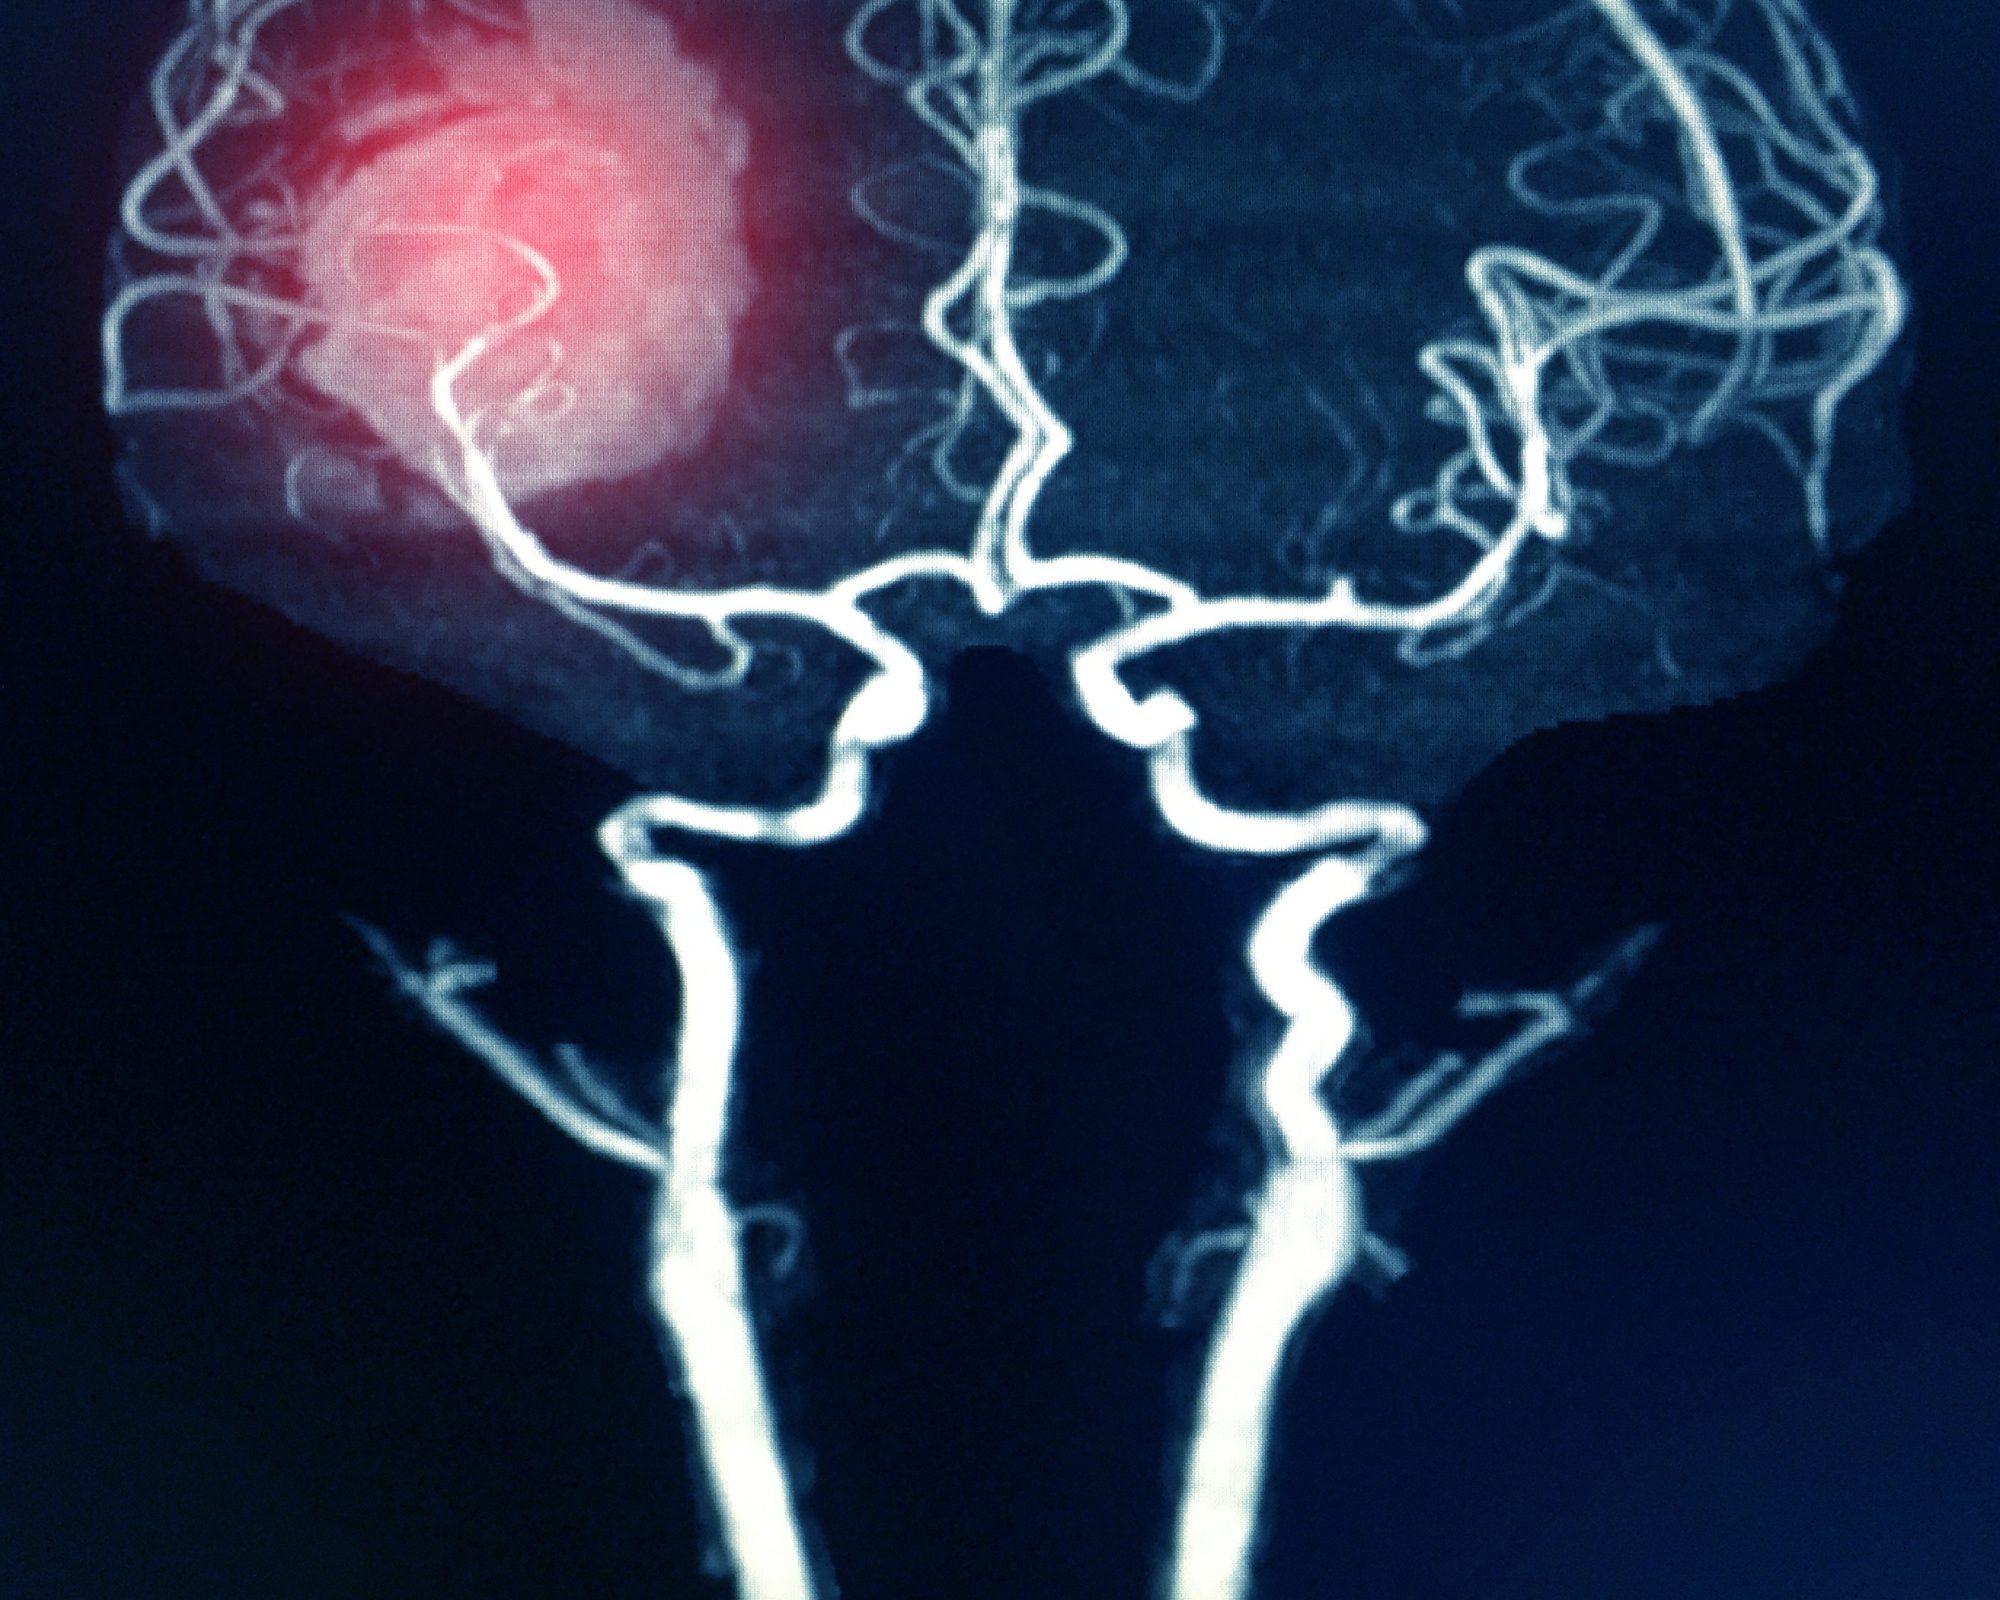

“Put simply, devices cause a radical change in the pathophysiology—in blood flow, in this case—that is visible, and demonstrable, immediately,” Liebeskind says. “A mechanical thrombectomy is very simplistic in that you can demonstrate, via an angiography, exactly what was done and at what timepoint. Angiography tells the story of both the therapeutic intervention as well as the subsequent diagnostic information.”